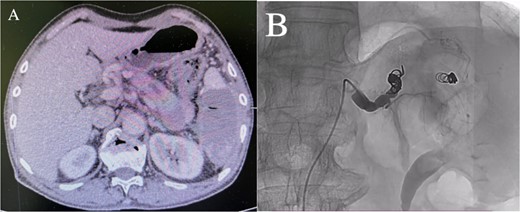

Enhanced CT showed regional portal hypertension and CP invading the splenic artery and forming a pseudoaneurysm of the splenic artery, partially invading the jejunum (Fig. 1A). Subsequent celiac angiography confirmed a pseudoaneurysm originating from the splenic artery (Fig. 1B). Combined with the characteristics of the patient’s history and the results of angiography, the patient was diagnosed with gastrointestinal bleeding: pseudoaneurysm of the splenic artery and CP. After excluding relevant contraindications, abdominal arteriography and embolization were performed simultaneously. So further intubation until confirmation of splenic artery angiography, we used a coil to embolize the pseudoaneurysm. At that time, repeat angiography showed that the main splenic artery and the pseudoaneurysm showed no further enhancement (Fig. 2B). Subsequent CT scan 6 days after the embolization showed no filling of the pseudoaneurysm (Fig. 2A), and he was discharged 2 days later. After 6 months of follow-up, the patient recovered well and returned to normal work and life.

(A) Abdominal CT scan showed the presence of a SAP. (B) Celiac angiography confirmed that the main trunk of the splenic artery showed contrast agent overflow and the formation of a pseudoaneurysm of the splenic artery.